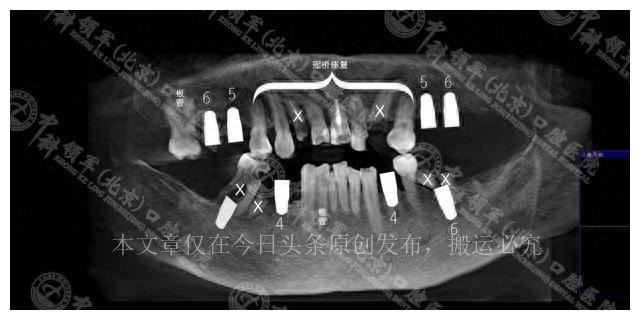

在医生的建议下,李女士面临两种选择。首先是保守治疗方案,它包括拔除6

颗有问题的牙齿,进行根管治疗,种植4颗缺失的牙齿,并对2颗需要修复的牙齿进行补牙,最后对上前牙区进行冠桥修复。这个方案虽然需要较多的复诊次数,总体费用为5.5万元,但保留了一部分原有的好牙,显然是一种相对保守的治疗方式。

另一方面,即拔即种的全口种植方案则更为激进。

它涉及拔掉上下两颗牙齿,然后种植12颗种植体。虽然这个方案费用较高,达到7万元,但只需要3次复诊,相对来说更为便捷。